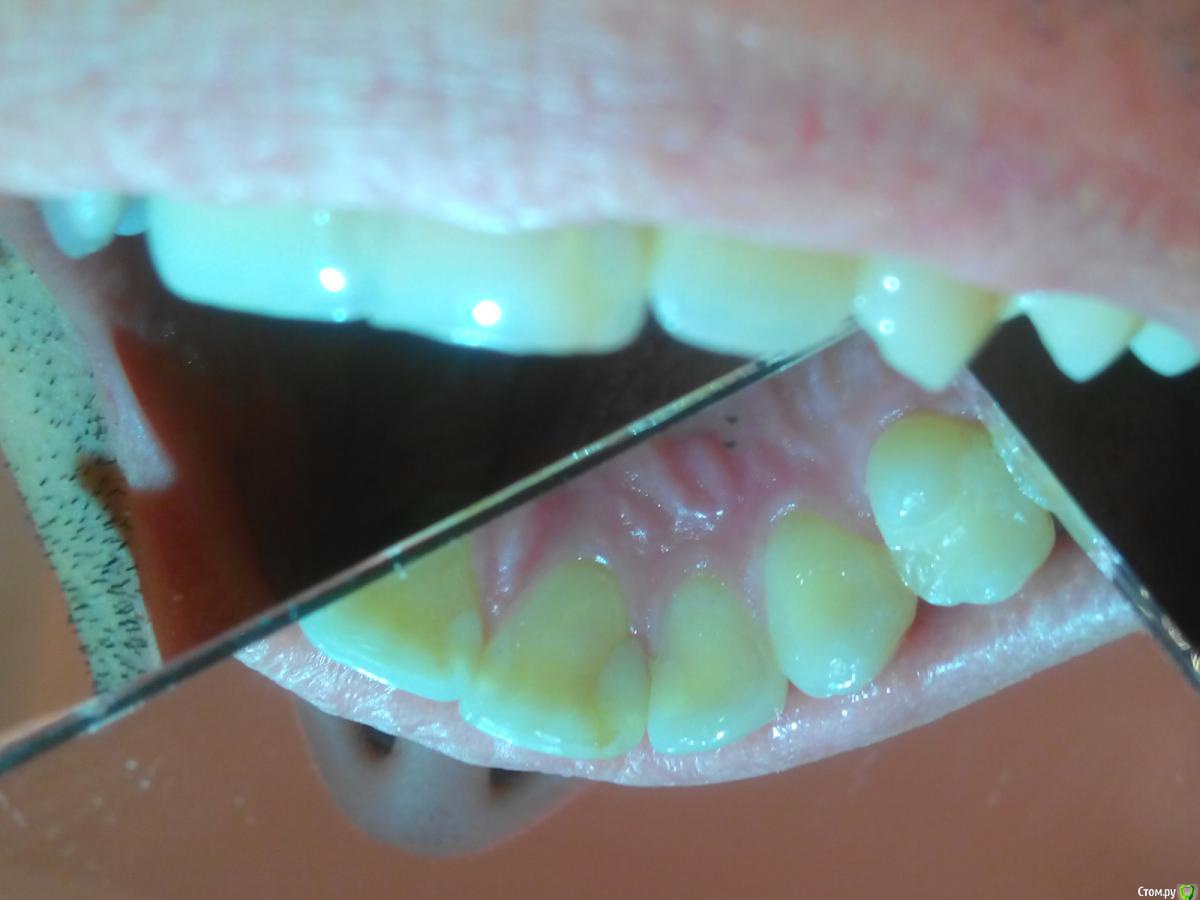

eizo Опубликовано 5 января, 2015 Поделиться Опубликовано 5 января, 2015 (изменено) Уважаемые специалисты и просто знатоки, помогите определиться по снимку на счёт наличия кариеса в 21м и/или 22м зубах. .Только что сделал снимок участка между 21м и 22м зубом (хотя снимок непонятный получился на мой взгляд).У меня уже 7 лет пломбав частив 21го зуба ближе к краю на границе с 22м. В середине ноября треснул 21й с нижней кромки, но болевых ощущений не было. Стоматолог в районнной ничего не смог предложить, ничего не обнаружил. Перед новым годом начали проявляться неприятные ощущения после приёма пищи, причём по собственным ощущениям именно на краю 22го со стороны примыкания к 21му.Сходил в другую клинику, терапевт сходу предположил рецидив кариеса в 21м, отвергая какие-либо дефекты в 22м.На снимке вроде бы ракурс с внутренней стороны челюсти (снимок производился с датчиком).Насколько я могу разобраться на 22м наблюдается дефект. А вот на счёт 21го -там где светлое пятно - это должна быть пломба. Изменено 5 января, 2015 пользователем eizo Ссылка на комментарий

SDC Опубликовано 5 января, 2015 Поделиться Опубликовано 5 января, 2015 Не самые лучшие фото и рг снимок, но однозначно есть дефект пломбы 21 зуба (нависание в придесневой области)и я почти уверен в том ,что есть рецидив кариеса. По 22 зубу - ничего сказать не могу. Ссылка на комментарий